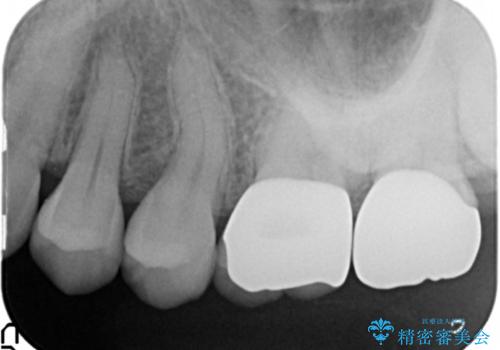

- 舌で触ると段差が大きく気になる銀歯の改善を求めて来院されました。

複雑な形態の銀歯の下には虫歯が再発しており、虫歯を丁寧に除去したのちジルコニアクラウンによる機能回復を行います。

- 22万円(仮歯・ジルコニアクラウン×2)費用は治療当時の料金となります

ジルコニアクラウンは金属を用いない審美的にも強度的にも優れたクラウンです。